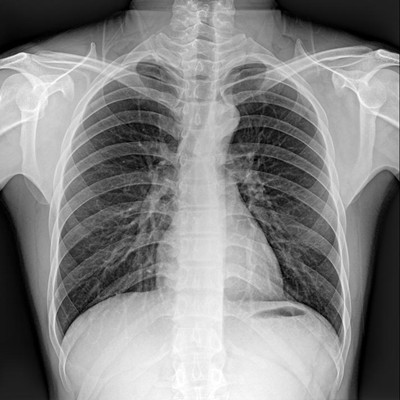

高品質(zhì)影像鏈 讓您看的更清晰 PLX8500C/D

●大尺寸非晶硅平板探測(cè)器。

●探測(cè)器可以大范圍轉(zhuǎn)動(dòng),大尺寸有效探測(cè)面積,可滿足人體多部位攝影需求。